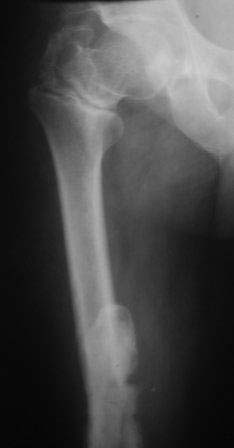

Уважаемые коллеги. Госпитализирован б-ной 47 лет, травма высотная 9 месяцев назад, тогда оперирован и/м остеосинтез (чрезвертельный перелом не диагностирован) в одном мед.объединение, через 3 месяца почему-то штифт удален. Больной ходит с двумя костылями, ногу не нагружает, выраженная патологическая подвижность в с/з бедра, в обл вертелов патологическую подвижность определить не удается, умеренная отечность всего бедра, укорочение около 4-5см. В плане в начале дистрактор, после устранения укорочение и репозиции БИОС реконструктивным стержнем( универсальным). Уважаемые коллеги помогите советом!, какие другие варианты, нюансы, случаи из практики! С уважением Абдурашид.

Наверное имеет смысл покачать бедро под ЭОПом и определить есть ли сращение чрезвертела.

Если нет, то Ваш план хорош- можно зафиксировать оба перелома. Если же чрезвертел сросся, то диафиз можно фиксировать ретроградно или LCP с костной пластикой.

На мой взгляд угол абсолютно не исправлен, а даже где-то уменьшился (106 гр. против 114), есть все условия для прорезывания шеечных винтов при нагрузке. Если открывали зону перелома, почему не выбрали в качестве импланта клинковую пластину?